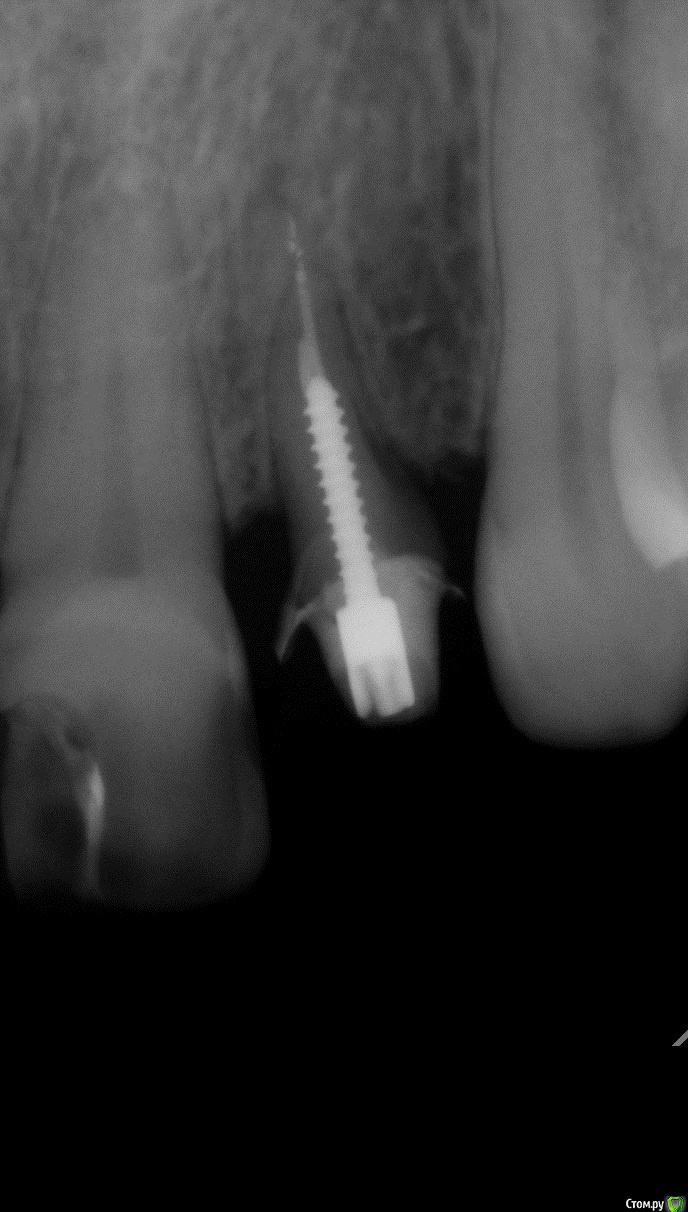

Sundance Опубликовано 9 июня, 2015 Поделиться Опубликовано 9 июня, 2015 Пациент категорически против удаления но пришлось временно удалить )))) и зафиксировать на мес. в новом положении через год с времянк ой 14 Ссылка на комментарий

Sundance Опубликовано 10 июня, 2015 Автор Поделиться Опубликовано 10 июня, 2015 Тогда зачем удалять, если можно вытянуть?результат почти одинаковій но здесь у корня еще дефект дистально нада было ево повернуть + так еще быстрее Ссылка на комментарий

Sundance Опубликовано 10 июня, 2015 Автор Поделиться Опубликовано 10 июня, 2015 И сколько по времени? при хирургической екструзии через 3 недели после удаления можно нагружать Ссылка на комментарий